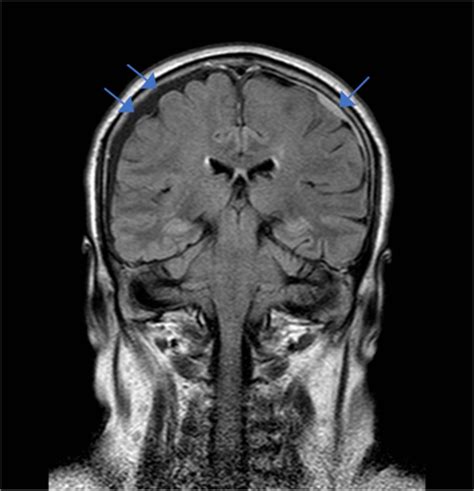

In some cases, imaging tests such as a CT scan or MRI may be ordered to rule out other potential causes of the headache, such as a hematoma or infection. A lumbar puncture may also be performed to measure CSF pressure and check for signs of infection.